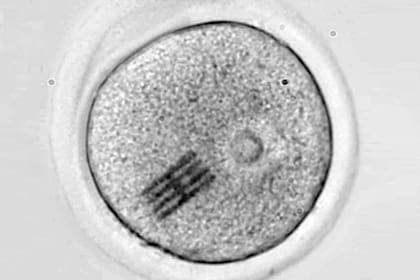

Investigadores del Instituto de Microelectrónica de Barcelona (IMB-CNM) del CSIC y la Universidad de Bath (Reino Unido) han fabricado e introducido chips dentro de células vivas para detectar los cambios mecánicos que se producen en las primeras etapas del desarrollo embrionario. Los detalles los publican esta semana en la revista Nature Materials.

El chip funciona como sensor mecánico y es extremadamente minúsculo: mide apenas 22 por 10,5 micrometros, con 25 nanometros de grosor. Esto significa que tiene una longitud tres veces más pequeña que el diámetro de un cabello humano, y un espesor tres veces menor que el de un virus como el SARS-CoV-2.

Los dispositivos se han fabricado en la sala blanca del IMB-CNM bajo la supervisión del científico José Antonio Plaza. Luego, en un laboratorio de la Universidad de Bath, otro equipo dirigido por Anthony C. F. Perry ha inyectado el chip junto con un espermatozoide en el interior de un óvulo de ratón para analizar las etapas tempranas de la fertilización. Este proceso inicial ocurre de forma similar en los humanos.

Con el dispositivo dentro, han podido medir las fuerzas que reorganizan el interior del óvulo, es decir, su citoplasma, desde que se introduce el espermatozoide hasta que se divide en dos células.

"Haciendo un símil con el baile, el embrión realiza una coreografía de movimientos durante su desarrollo y hemos visto que no sólo el movimiento es importante sino también la intensidad del mismo", comenta Plaza, "y a través de microscopia, podemos ver cómo el chip se dobla en el interior de la célula".

"Dado que hemos modelizado y conocemos perfectamente qué fuerza hay que aplicar para que se doble el chip de una determinada manera –añade–, visualizando la curvatura podemos inferir qué fuerzas mecánicas se están dando en el interior celular".